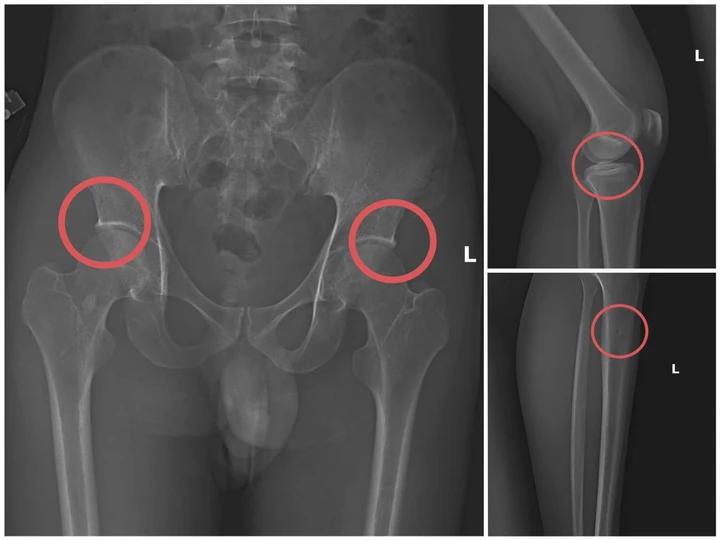

Bản phim chụp XQ một số tổn thương xương do đối tượng tạo ra. (Ảnh: Công an tỉnh Phú Thọ).

Đáng chú ý, Châu trực tiếp thực hiện hành vi tiêm thuốc mê, rồi dùng kim tiêm, búa... để tác động vào xương người mua bảo hiểm, tạo nên các vết nứt, vỡ xương tương tự tai nạn thật.

Khi thương tích tạo xong, Châu tiếp tục hướng dẫn các đối tượng dựng hiện trường giả như điện giật ngã, trượt chân ngã suối nhằm hợp thức hóa bệnh án và hoàn thiện hồ sơ yêu cầu chi trả.

Theo đánh giá của Giám đốc Công an tỉnh, thủ đoạn này vừa tàn nhẫn, vô nhân tính, coi thường sức khỏe, tính mạng của người tham gia, vừa được tính toán kỹ để gây thương tích đúng vị trí có mức chi trả cao, khiến các công ty bảo hiểm khó phát hiện dấu hiệu gian dối.